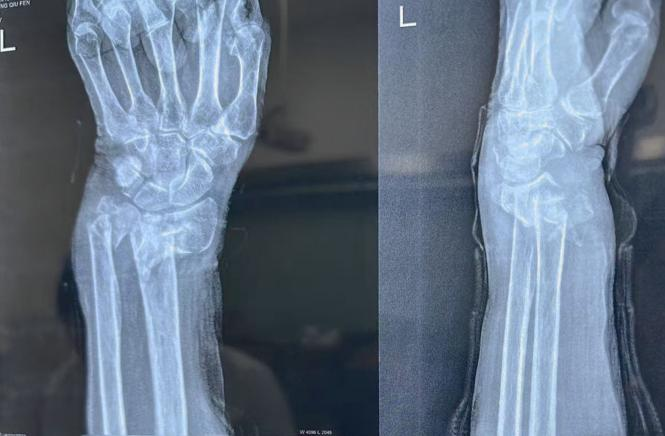

12月24日早晨7点,老人在家中起身时不慎摔倒,左手腕重重着地,剧痛让她当场呻吟不止。家人发现时,老人左腕已迅速肿胀变形,皮肤浮现大片紫青色瘀斑,连抬手都难以完成,随即被送往附近医院。X光检查显示,老人左尺桡骨粉碎性骨折,骨折端碎裂成多块且明显移位。考虑到患者高龄、骨质疏松严重,手术风险较大,家属在多方咨询后,果断转往以骨科闻名的西安市红会医院,寻求手法复位治疗。

此时距受伤已超7小时,老人左腕肿胀如馒头,瘀斑蔓延至小臂,触诊可清晰感知骨折碎块异常活动,轻微挪动便引发钻心疼痛。接诊的薛安邦医生迅速检查、调取X光片,并紧急联系手法复位室主任董博、副主任医师周健会诊。“患者骨折碎块多、移位明显,加之高龄骨质疏松、软组织肿胀加剧,手法复位难度堪比‘针尖上跳舞’。”董博主任指着X光片上的碎骨分析道,“但手术对老人身体负担大,我们必须尽力尝试手法复位,减少创伤。”随后,三位医生围绕影像反复推演,精准制定牵引力度、折顶角度等细节方案。

复位操作紧张有序展开:周健副主任医师稳握老人前臂反向牵引,把控力度与节奏,逐步拉开移位骨折端;董博主任专注腕部,对碎裂骨块精准实施折顶、旋转、推挤,手指灵活感知骨块位置变化;薛安邦医生密切观察老人面色、心率与反应,适时提醒调整力度,并用温和话语安抚分散其注意力。随着一声轻微的“咔嗒”骨擦音,移位的骨折碎块精准归位,老人呻吟声戛然而止,眉头舒展。 当董博主任宣布“复位成功”时,诊疗室里的众人都松了一口气,随即医护人员为患者进行石膏固定。复查X光片显示,骨折端对位对线良好,复位效果远超预期。